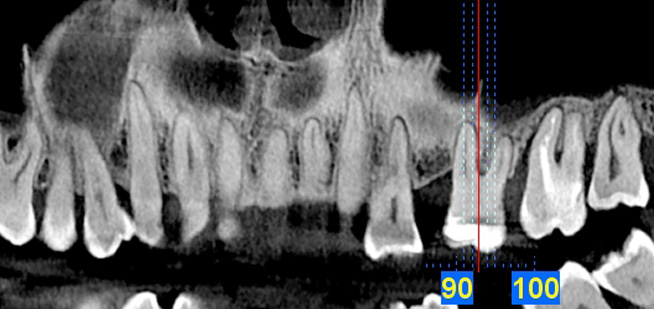

Endo-Perio

Der Facharzt für Endodontie und Periodontologie benötigt Bilder von absoluter Spitzenqualität und Detailschärfe, um Verfahren wie die Behandlung von Zahnbrüchen, die Heilung von Zahngewebe und die Therapie des Kieferkanals vorzunehmen, da er über genaue Details der behandelten Zone und des Krankheitsbilds verfügen muss, um eine wirkungsvolle Behandlung planen zu können. Nur eine eingehende Untersuchung der betroffenen Areale kann Aufschluss über einen mehr oder weniger invasiven Eingriff geben.